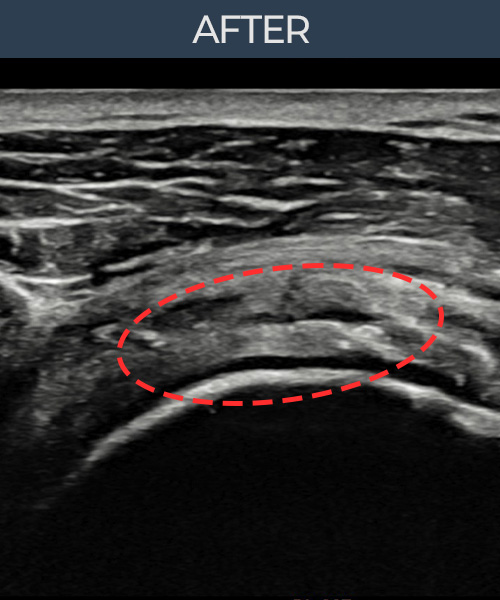

최ㅇㅇ님 · 우측 극상근건 점액낭면측 부분파열

우측 어깨 통증이 수개월간 지속되어 내원하셨습니다. 초음파 검사에서 점액낭면측 극상근건 부분파열이 확인되었으며, 어깨인대 축소봉합술 후 힘줄 두께가 회복되고 에코 연속성이 정상화되었습니다.